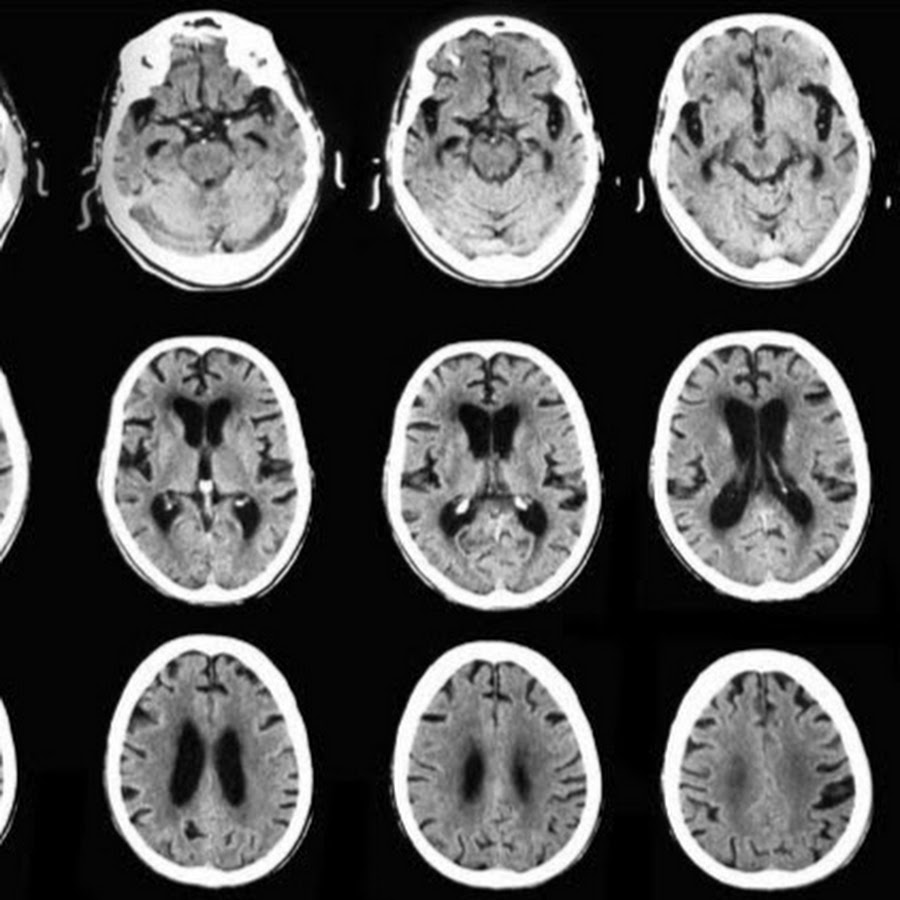

Кт общее